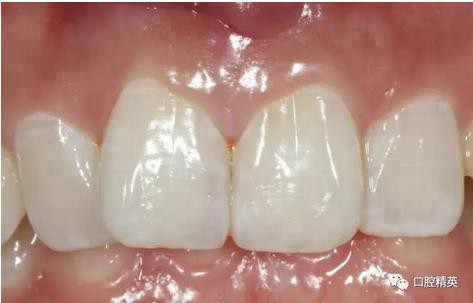

口內(nèi)正側(cè)位及切端特寫

從側(cè)位照可看出遠(yuǎn)中切角略有回收

對(duì)比來看基本達(dá)到患者預(yù)期

有一點(diǎn)不足之處在于齦緣的高低不完全一致,補(bǔ)救辦法同上——激光輕掃